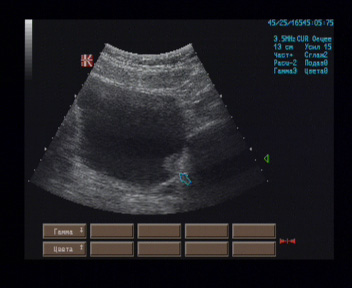

Мочевой пузырь симметричной овальной формы, наружные контуры ровные, V мочи 300 мл, стенка толщиной 5 мм, на внутренней поверхности задней стенки лоцируются два изогипоэхогенных образования, расположенные вблизи шейки, в 12 мм друг от друга, размерами 15 х 11 х 19 мм и 12 х 10 х 9 мм, а также двух узлов в проекции шейки – размерами 12 х 9 х 9 мм и передней стенки вблизи шейки размерами 19 х 15 х 13 мм, имеющие широкие основания, овальные формы, однородное внутреннее строение, на остальном протяжении внутренняя поверхность пузыря гладкая, просвет свободный.

Эхографические признаки многофокусного новообразования мочевого пузыря.